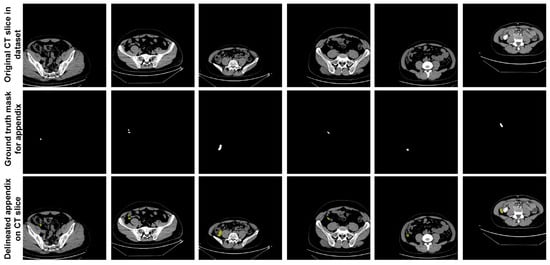

In the dataset, expert physicians annotated the appendix regions with ground truth (GT) masks in these CT scans, using ITK-SNAP software [], and the annotations were stored in NIfTI format. During the data preparation phase, axial slices identified by the expert physicians as containing the appendix were extracted. This process resulted in 672 slices from patients with appendicitis and 748 slices from healthy individuals, giving a total of 1420 slices extracted. These annotated slices formed the basis of the dataset used to train and evaluate the proposed U-Net deep learning model. Figure 2 shows sample slices from the dataset, indicating the annotated appendix regions with GT masks. This dataset, with its detailed annotation and diverse sample population, provided a robust approach for training the U-Net model to accurately segment the appendix in CT images.

Figure 2.

Sample slices from the dataset indicating the annotated appendix regions with GT masks.